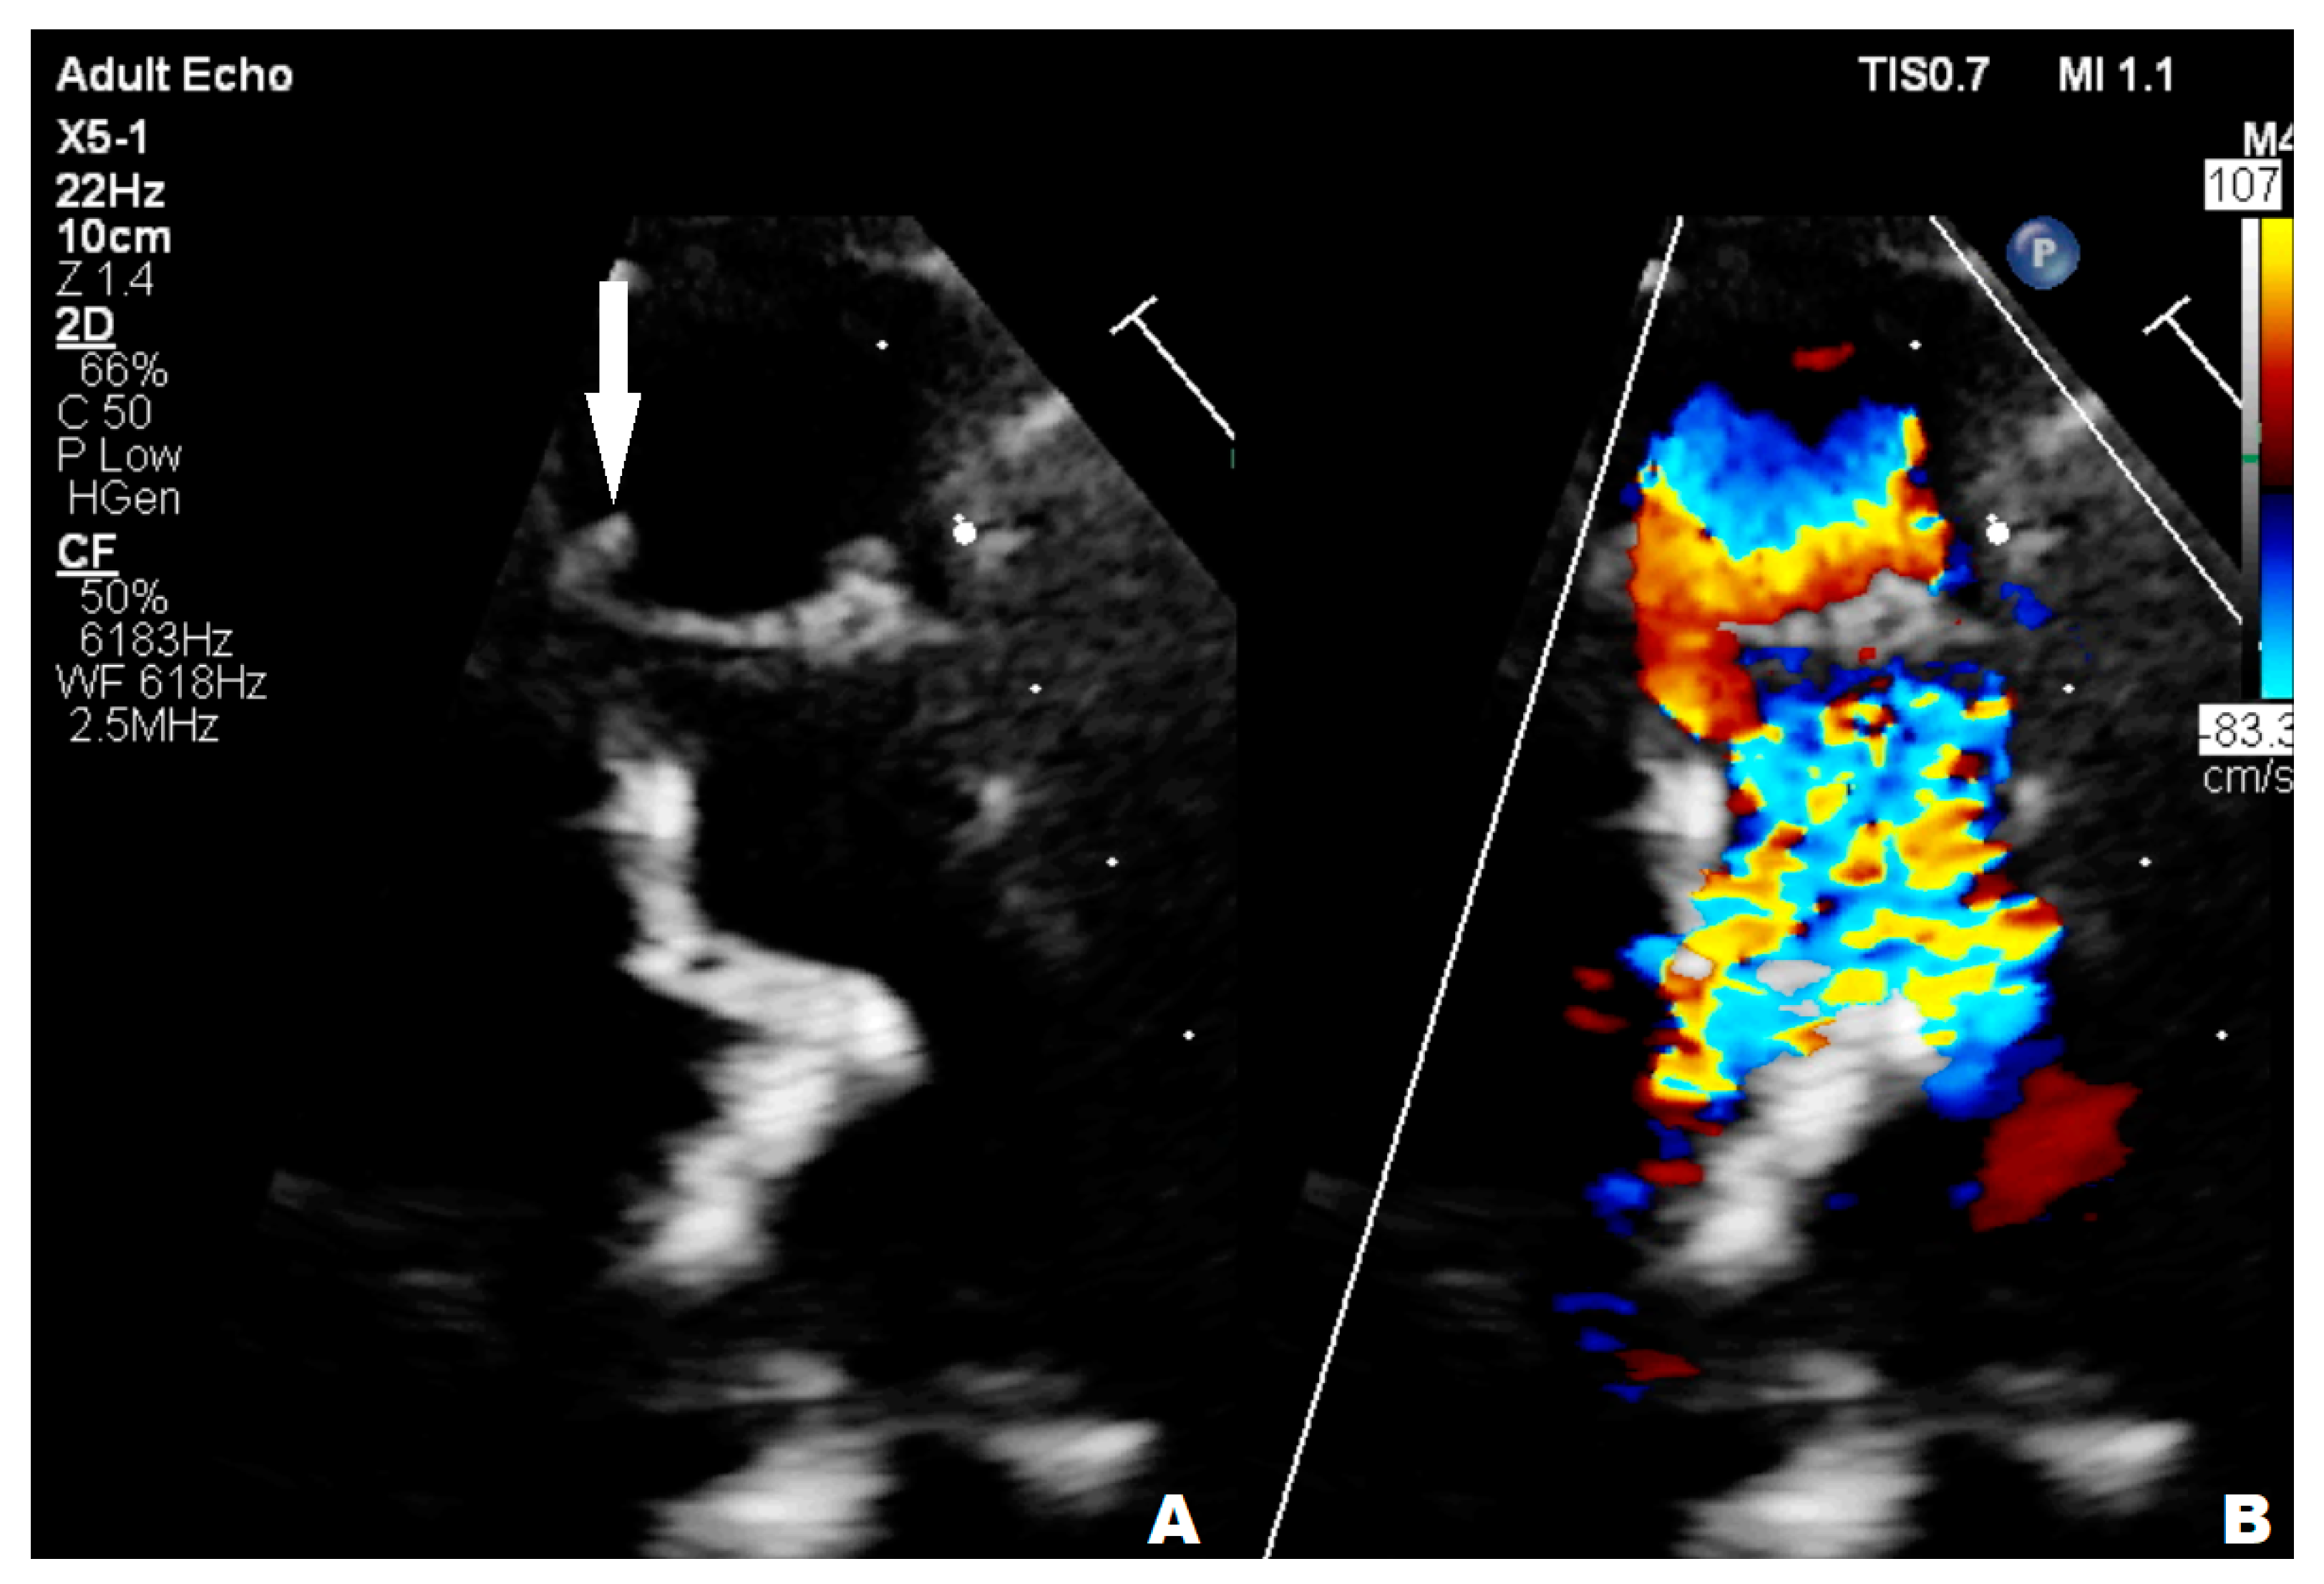

A nearly-16-year-old girl was admitted to the Pediatric Department because of recurrent fever and hepatosplenomegaly. In the past, the girl had undergone procedures such as complete Fallot Tetralogy repair during infancy, Contegra replacement by CorMatrix conduit in pulmonary position during her preschool years, numerous catheter interventions with percutaneous stenting of LPA, and Resilia 23 Edwards implantation two years before her current hospitalization in the Pediatric Department. The patient had suffered from frequent respiratory system infections, recurrent fever, anemia, and microhematuria with cast erythrocytes in urine for the last six months. The teenager did not present other symptoms; however, the clinical examination revealed a systolic heart murmur of 3/6 in LS over the PV, and a significantly enlarged liver and spleen. CRP (20.40 mg/L) and erythrocyte sedimentation rate (45 mm/1 h, 78 mm/2 h) (ESR) were slightly elevated but hemoglobin (7.2 g/dL) (HGB) and erythrocyte mean corpuscular volume (71.0) (MCV) levels were significantly decreased. The treatment started with ceftriaxone (2 g twice/day), then cefixime (400 mg/day) was administered and two units of packed red blood cells were transfused. The patient was transferred to two upper reference departments because of insufficient CRP and the decrease in other inflammation indicators levels and persistent HGB level, where initially the formerly-administered antibiotic therapy was continued. The patient’s general clinical state was stable; the ankles were slightly swollen. Microhematuria with casts erythrocytes, proteinuria (76.9 mg/dL), and elevated levels of protein in 24-h urine (172.50 mg/dL) collection were seen; eGFR was mildly reduced (60 mL/min/1.73 m2). Creatinine (1.57 mg/dL), urea (39.0 mg/dL), rheumatic factor (216 Iu/mL) (RF), CRP (20.00 mg/L), lactate dehydrogenase (313 U/L) (LDH), and d-dimer (1893 μg/L) levels were elevated. The antinuclear antibodies (+) (ANA) screening was slightly positive but anti-neutrophil cytoplasmic proteinase 3 antibodies (PR3-ANCA) were highly positive (+++). All the results of the blood culture samples taken according to the ESC procedure were negative. The former antibiotic therapy was replaced with cloxacillin (firstly 2 g, 6 times/day, next 3 g, 4 times/day), ampicillin (firstly 2 g, 6 times/day, next 3 g 4 times/day), and ceftazidime (2 g, 3 times/day). The teenager’s liver and spleen were still enlarged, the kidneys and pelvicalyceal system were in ultrasonographical normal condition, and an insignificant ovarian cyst was visible on abdominal ultrasonography. The TTE examination showed the hypertrophied and dilated RV, reduced RV ejection fraction (EF), enlarged right atrium (RA), reduced IVC respiratory variability, abnormal interventricular septal motion, II degree tricuspid regurgitation with PG 100 mmHg, II degree PV regurgitation with max 36 mmHg, and right ventricle outflow tract (RVOT) stenosis with maximum PG 60 mmHg. The 2.5 mm and 3 mm slightly-built ballotable vegetations were weakly visible on Resilia in TTE (Figure 4A,B), but in TOE all vegetations were well-visible.

Figure 4.

Transthoracic echocardiography; (A) the arrow point at ballotable vegetations; (B) II degree PV regurgitation; PV—pulmonary valve.